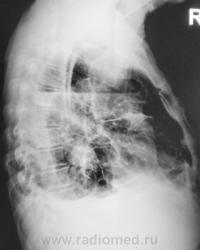

- https://radiomed.ru/sites/default/files/styles/case_slider_image/public/user/12/2.pb130018.jpg?itok=qpNgo3K0

- https://radiomed.ru/sites/default/files/styles/case_slider_image/public/user/12/3.pb130020.jpg?itok=ZQIONPdk

Я так понимаю , что справа - это случайная находка ( C-r нижнедолевого бронха , осложненный субателектазом правого легкого и правосторонним гидропневмотораксом) ?

Нет. Это ДТП.

Интересно, был ли снимок до установки подключички справа?

Снимок был сделан на передвижке, качества ниже "хренового", но уже тогда газ в плевральной полости справа был, была с обеих сторон огроменная подкожная и межмышечная эмфизема.